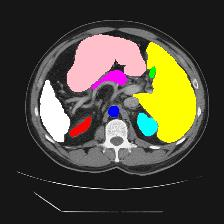

Medical image segmentation is one of the most fundamental tasks concerning medical information analysis. Various solutions have been proposed so far, including many deep learning-based techniques, such as U-Net, FC-DenseNet, etc. However, high-precision medical image segmentation remains a highly challenging task due to the existence of inherent magnification and distortion in medical images as well as the presence of lesions with similar density to normal tissues. In this paper, we propose TFCNs (Transformers for Fully Convolutional denseNets) to tackle the problem by introducing ResLinear-Transformer (RL-Transformer) and Convolutional Linear Attention Block (CLAB) to FC-DenseNet. TFCNs is not only able to utilize more latent information from the CT images for feature extraction, but also can capture and disseminate semantic features and filter non-semantic features more effectively through the CLAB module. Our experimental results show that TFCNs can achieve state-of-the-art performance with dice scores of 83.72\% on the Synapse dataset. In addition, we evaluate the robustness of TFCNs for lesion area effects on the COVID-19 public datasets. The Python code will be made publicly available on https://github.com/HUANGLIZI/TFCNs.

翻译:医学图像分解是医学信息分析的最根本任务之一,到目前为止已经提出了各种解决办法,包括许多深层次的学习技术,如U-Net、FC-DenseNet等。 然而,高精度医学图像分解由于医疗图像中存在固有的放大和扭曲,以及存在与正常组织密度相似的损伤,因此仍是一项极具挑战性的任务。在本文件中,我们建议TFCN(全面革命稠密网络的传输者)通过向FC-DenseNet引进ResLear-Transerferent(R-Transerfor)和Culvacial线性关注区(CLAB)来解决这一问题。TFCN不仅能够利用CT图像中更多的潜在信息来提取特征,而且还能够通过CLAB模块更有效地捕捉和传播语性特征和过滤非神经性特征。我们的实验结果表明,TFCN可以在Syapseion/SymblyDDS上以83CN-72 ⁇ 的分数实现状态。此外,我们在Synapse-DRIS数据设置上,我们还将评估CUTFTFI/LIS的可靠度。